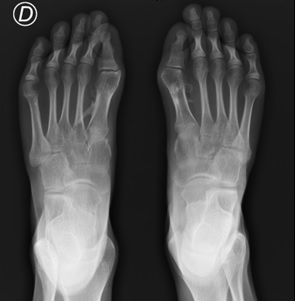

Displasia metafisaria múltiple. Reporte de caso

Jennifer Richardson Maturana, Martha E. Oyuela-Mancera, José A. Ovalle-Barranco

28-32